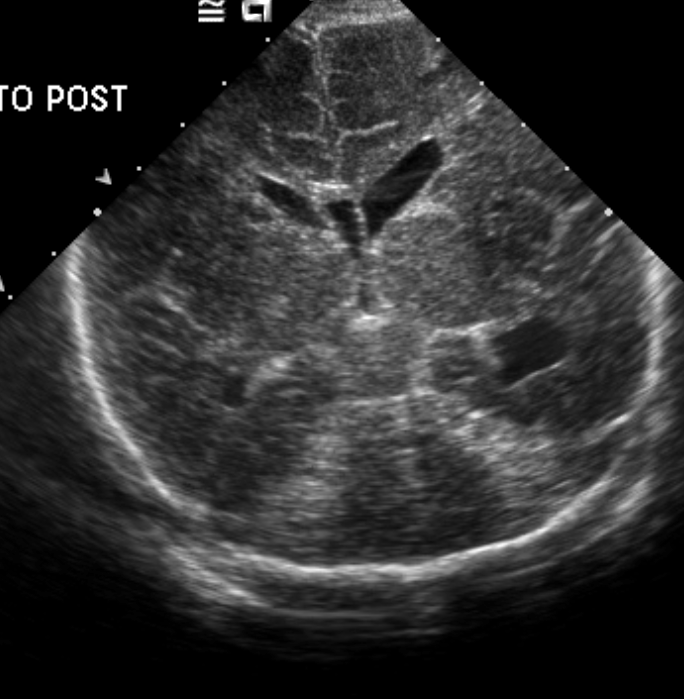

Info Images Findings Impression Reco/Acuity Case Images View Images / Launch Visage Case Notes History Full term infant. We are asked to evaluate posterior fossa cyst. Exam Gray scale and Doppler Ultrasonographic examination of the head. Prior Study N/A Dicom View Reference Material

Section 1 Submit Findings Case149 Findings Brain The brain is immature. Yes No There is under-sulcation and open sylvian fissures. Yes No There is/are multiple hypoechoic areas in the periventricular white matter. Yes No There is/are multiple hyperechoic areas in the periventricular white matter. Yes No There is diffuse cerebral edema with diffusely increased echogenicity of the brain parenchyma and loss of grey white matter differentiation. Yes No The thalami/basal ganglia are hypoechoic. Yes No There is periventricular calcification. Yes No There is intra-parenchymal calcification. Yes No CSF spaces/ventricular system There is a prominence of the extra axial fluid spaces. Yes No There are debris/septations in the extra axial fluid spaces. Yes No There are debris/septations in the ventricles. Yes No There is a subdural collection on the right/left side. Yes No There is prominence of the ventricular system. Yes No There is an asymmetry of the ventricular system. Yes No There is a cavum septum pellucidum. Yes No There is a midline shift towards right/left. Yes No The choroid plexus is bulky/lobulated. Yes No There is a choroid plexus cyst measuring… Yes No There are debris/clots in the occipital horn. Yes No There is a posterior fossa cyst measuring… Yes No The tentorium is elevated/depressed. Yes No The lateral ventricle/s are dilated. Yes No The third ventricle is dilated. Yes No The 4th ventricle is dilated. Yes No There are pseudo cysts. Yes No Germinal matrix hemorrhage (Only in the premature infants): Please do not answer if the patient is a full term. There is a germinal matrix hemorrhage, consistent with a grade I hemorrhage. Yes No There is an intraventricular extension consistent with a grade II hemorrhage. Yes No There is an intraventricular extension with the dilatation of ventricles, consistent with a grade III hemorrhage. Yes No There is an intra-parenchymal extension, consistent with grade IV hemorrhage. Yes No On color Doppler examination, the Resistive index in the anterior cerebral artery is… There is a loss of the diastolic flow on the Doppler exam. Yes No There is altered vascularity on Doppler imaging. Yes No There is an AVM in the region of… Yes No